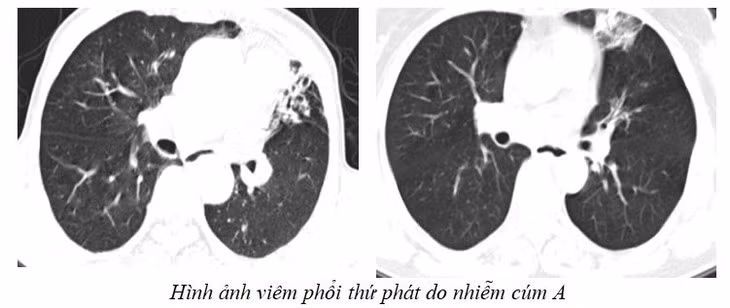

Các biến chứng có thể gặp gồm: viêm phổi tiên phát do virus, viêm phổi thứ phát do vi khuẩn, viêm cơ tim, viêm màng ngoài tim, viêm cơ, hội chứng Reye, viêm xoang…

Phổi trắng xóa vì mắc cúm A: Điều trị, kiêng gì nhanh hồi phục?

Hiện các bệnh viện trên địa bàn Hà Nội đang rất đông bệnh nhân đủ mọi lứa tuổi đi khám và phải nằm viện vì cúm A biến chứng nặng.

Cúm A dễ biến chứng suy hô hấp, viêm phổi, viêm tai giữa, viêm não, viêm cơ tim, viêm thanh khí phế quản, nhiễm khuẩn thứ phát... và nguy cơ tử vong” - BS Phạm Văn Phúc, Phó trưởng Khoa Hồi sức tích cực, Bệnh viện Bệnh Nhiệt đới Trung ương nói.